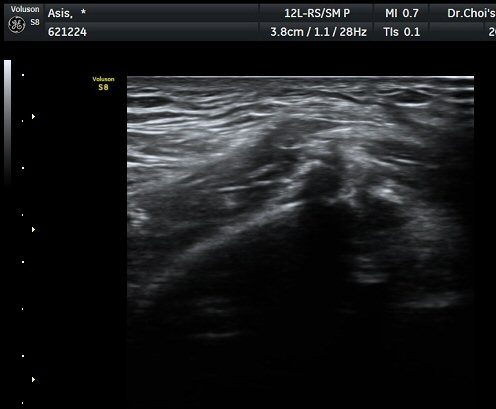

°üÂûµÇ°í(±×¸² 1) ¿ÜÃø´ëÅð±ÙÇǽŰæÀÇ ºÎÁ¾ÀÌ °üÂûµÊ(±×¸² 2, 3). Àü»óÀå°ñ±Ø Ⱦ´Ü¸é°Ë»ç¿¡¼­

°ß¿­°ñÀýµÈ °ñÆí°ú ¿ÜÃø´ëÅð±ÙÇÇ½Å°æ ºÎÁ¾ÀÌ °üÂûµÊ(±×¸² 4).